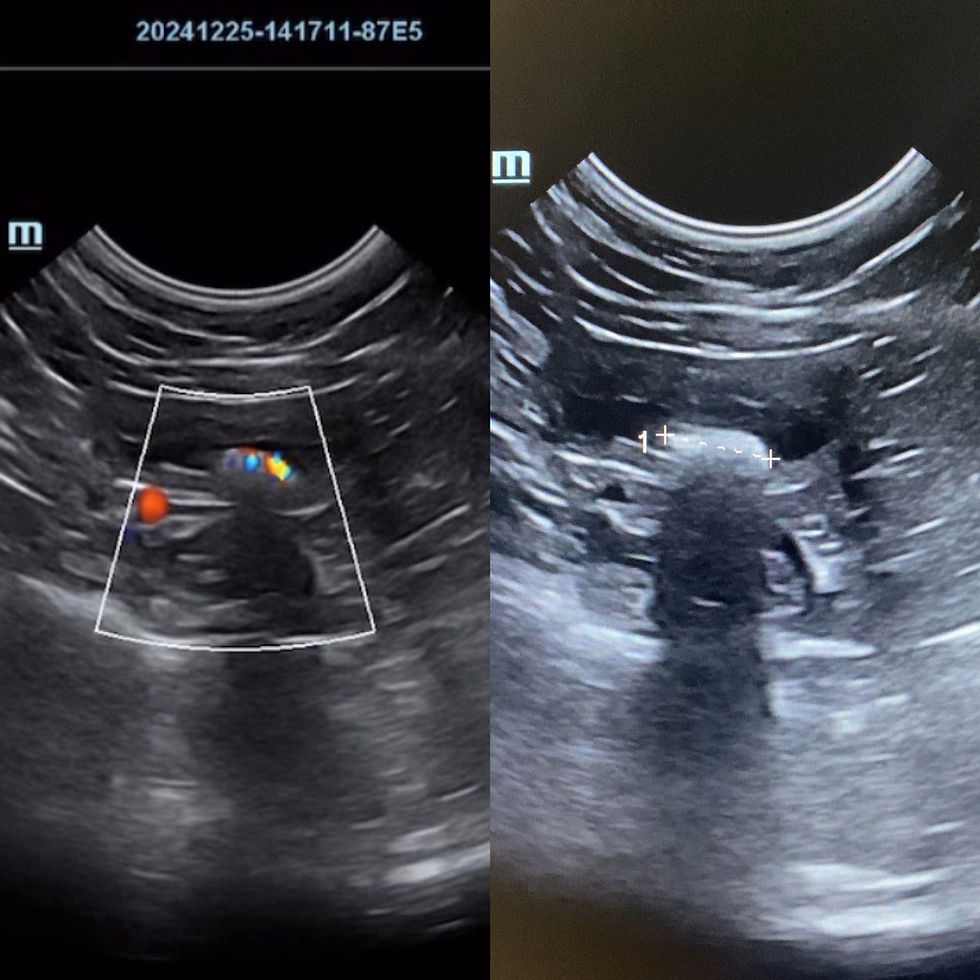

Geçtiğimiz günlerde kliniğimize gelen tatlı mı tatlı 8 yaşındaki Prenses, anal kese problemleri nedeniyle muayeneye alındı. Her zamanki gibi detaylı bir kontrol yaparken, karın içi organlarını da değerlendirmek adına bir abdominal ultrasonografi (USG) uyguladık. Anal kese sorununu çözdükten sonra, dalakta küçük ama dikkat çekici bir oluşum fark ettik: hiperekoik (ultrasonda parlak görünen), düzgün sınırlı bir nodül.

Ultrasonda:

• Parlak (hiperekoik) görünür,

• Düzgün sınırlıdır,

• Genellikle dalak kenarında ya da damarlar çevresinde yer alır,

• Bazen sayıca fazla olabilir ama çoğu zaman hiçbir belirtiye yol açmaz.